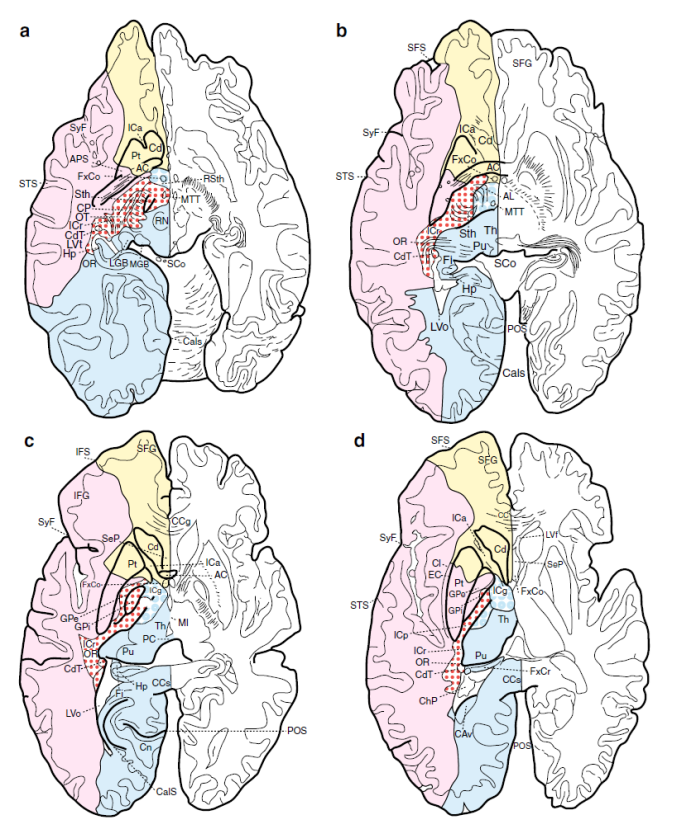

Cerebral vascular territories